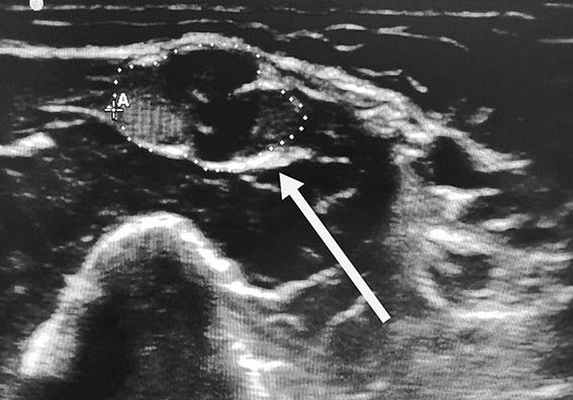

Клиническое наблюдение. Мальчик В., 2010 года рождения, с неотягощенным семейным анамнезом и без особенностей раннего развития. В возрасте 6,5 года мать впервые отметила, что ребенок без видимых причин начал прихрамывать на левую ногу. Неврологом в поликлинике было предположено поражение левого седалищного нерва, для уточнения генеза которого ребенок был направлен на УЗИ, которое не выявило изменений на доступном визуализации отрезке нерва.

Результаты осмотра, УЗИ периферических нервов и ЭМГ констатировали поражение на уровне пояснично-крестцового сплетения. Для уточнения причины изменений проведено МРТ с контрастным усилением гадолинием, обнаружено увеличение нервных стволов и накопление контрастного вещества в пояснично-крестцовом сплетении (рис. 2). Рис. 2. Тот же пациент. МРТ пояснично-крестцового сплетения в режиме Т1 с контрастным усилением гадолинием. МРТ плечевого сплетения не выявило изменений.